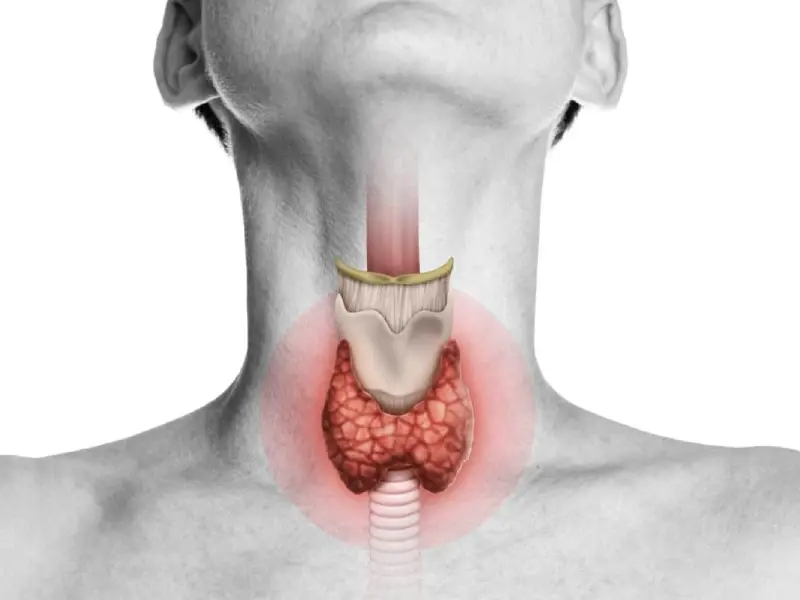

تیروئید فرمانده پنهان انرژی بدن

تیروئید غدهای کوچک در گردن است که با تنظیم هورمونها، سرعت کار کل بدن را کنترل میکند و کمکاری یا پرکاری آن تعادل بدن را بههم میزند.